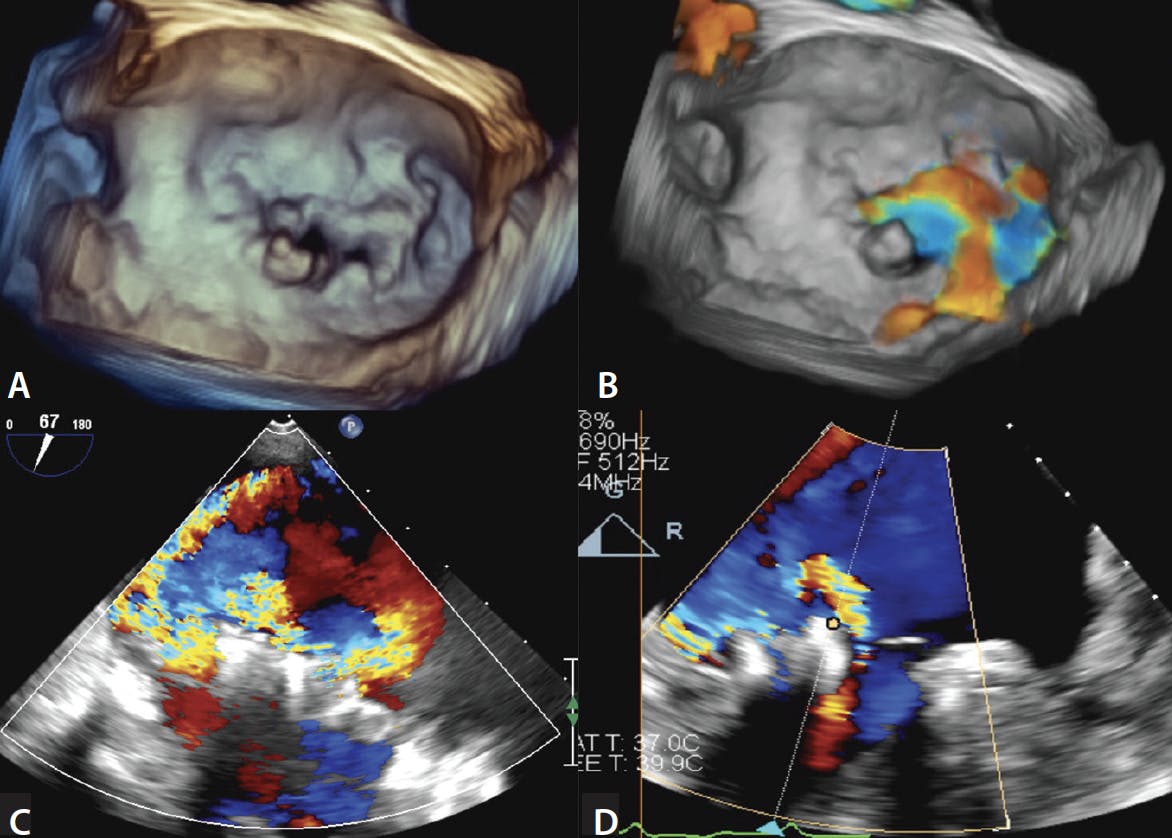

Patients with complex mitral valve pathology, such as Barlow disease with multiple prolapsing segments associated with multiple jets, may have suboptimal MR reduction with TEER, even with current-generation devices (Figure 4). Similarly, patients with active endocarditis or sequelae of previous endocarditis with perforation are other examples of cases in which TEER may not result in a meaningful reduction in MR. These patient subsets should be reconsidered for surgery if the risk is not prohibitive. Patients with a short posterior leaflet (< 5 mm) in the grasping zone such that there is not enough tissue to securely grasp are at risk of SLDA or leaflet injury. These patients may not have a durable result because TEER relies on apposition of ≥ 6 mm of leaflet tissue for stable implantation. Instead, such patients may be better served by TMVR.

Figure 4. TEE images of a patient with severe degenerative MR and Barlow disease with multiple prolapsing segments and MR jets. Baseline 3D TEE (A). 3D TEE with color (B). The patient was initially treated with XTR and NTR clips with moderate MR (not shown). TEE showing severe recurrent MR 1 year later (C). TEE after redo MitraClip XTR with moderate MR (D).